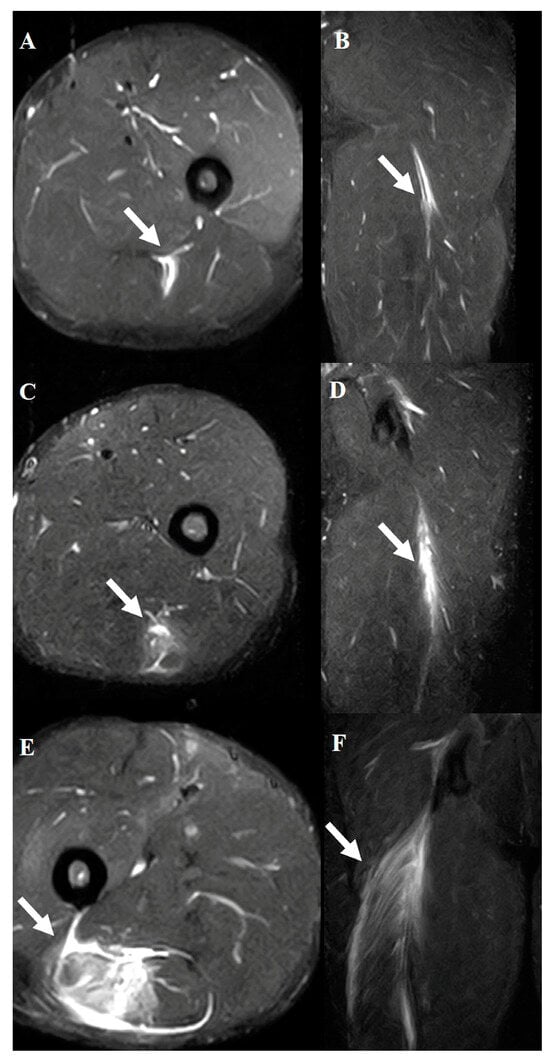

3.4. Impact of Injury Severity on Return to Sport Based on MRI Analysis

4. Combined Analysis of Injury Location and Severity

- The recovery times showed distinct differences depending on the injury location:

- Tendon grade 3 injuries required the longest recovery time, averaging 383 days, and differed significantly from all other groups (p < 0.001).

- Musculotendinous junction grade 3 injuries had a recovery time of 100 days, which was significantly longer than that in most other groups, except for tendon grade 3 injuries (p < 0.01).

- The groups with musculotendinous junction grade 2 and tendon grades 1 and 2 injuries showed similar recovery times, ranging from 57 to 65 days.

- Muscle grade 1 injuries had the shortest recovery time, averaging 16 days.